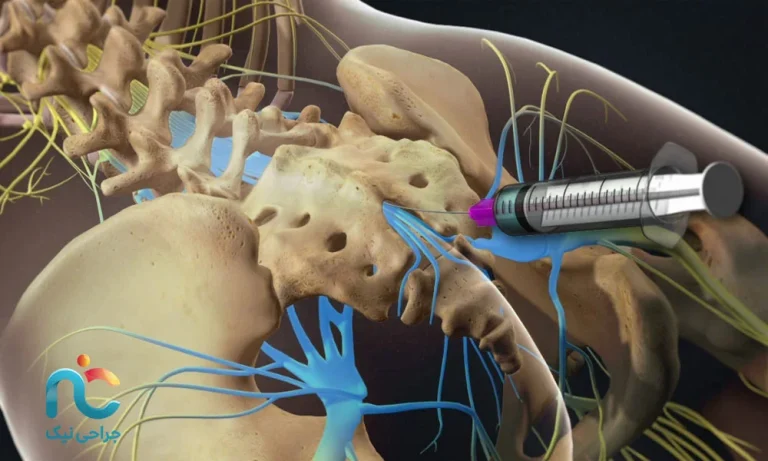

اول از همه، بیایید درباره کلمه «اپیدورال» صحبت کنیم. در ستون فقرات شما، نخاع و ریشههای عصبی داخل یک کانال استخوانی محافظ قرار گرفتهاند. بین این اعصاب و دیوارهی استخوانی، لایههایی محافظ وجود دارد. فضای باریک و نرمِ بین این لایهها و استخوان را «فضای اپیدورال» مینامیم. یعنی وقتی میگوییم تزریق اپیدورال، منظورمان این است که دارو در همین فضای اطراف اعصاب تزریق میشود، نه داخل خود نخاع. به زبان ساده، انگار دارو را در راهروی اطراف سیمهای اصلی عصبی تزریق میکنیم تا التهاب و فشار اطراف آنها کم شود و درد کاهش پیدا کند.

حالا «کودال» به چه معنی است؟ کودال در واقع به ناحیهی انتهای ستون فقرات، نزدیک دنبالچه، اشاره میکند. در تزریق اپیدورال کودال، ما به جای اینکه از وسط کمر وارد شویم، از پایینترین قسمت ستون فقرات، یعنی همان حوالی دنبالچه، وارد فضای اپیدورال میشویم. دلیل این انتخاب این است که از این مسیر، میتوانیم دارو را در بخش وسیعتری از فضای اپیدورال کمر پخش کنیم و به ریشههای عصبیای که باعث درد کمر و انتشار درد به پا (مثل سیاتیک) شدهاند، نزدیکتر شویم.

اما خودِ روند انجام تزریق چگونه است؟ این کار در یک مرکز مجهز و در اتاق مخصوص، بهصورت سرپایی انجام میشود. بیمار معمولا روی شکم یا در بعضی شرایط خاص روی پهلو قرار میگیرد و ناحیهی پایین کمر و دنبالچه ضدعفونی میشود و با مقدار کمی داروی بیحسی موضعی، پوست آن ناحیه بیحس میگردد تا هنگام ورود سوزن، درد زیادی احساس نشود. سپس پزشک با کمک دستگاه تصویربرداری (مثل فلوروسکوپی (اشعه ایکس) یا در برخی موارد سونوگرافی)، سوزن را از ناحیهی نزدیک دنبالچه به فضای اپیدورال هدایت میکند و پس از اطمینان از قرار گرفتن در محل مناسب، ترکیب دارویی را بهآرامی تزریق میکند.